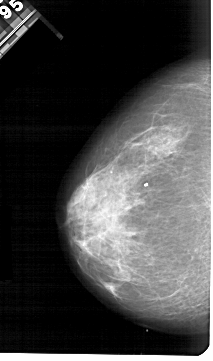

A_1533_1.RIGHT_MLO

RIGHT_MLO LINES 5491 PIXELS_PER_LINE 3181 BITS_PER_PIXEL 12 RESOLUTION 43.5 OVERLAY